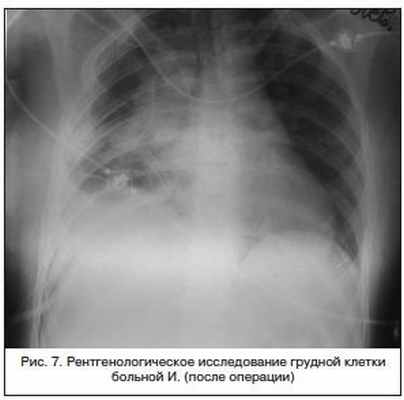

При рентгенологическом исследовании 16.02.2012 (рис. 7): определяются линии скобочного шва, в правой плевральной полости шварты, очаговых и инфильтративных теней нет.

Патогистологическое исследование № 450/22: зрелая терато-дермоидная киста (в полости кисты кожа и волосы). Прилегающая ткань фиброзирована с признаками ангиоматоза и выраженного полнокровия, остатками ткани тимуса.

При контрольном осмотре через 1 мес. – жалобы на умеренные боли в области торакотомного разреза (рубец без признаков воспаления), температура тела в норме, рентгенологически определяются линии скобочного шва, очаговых и инфильтративных теней нет.